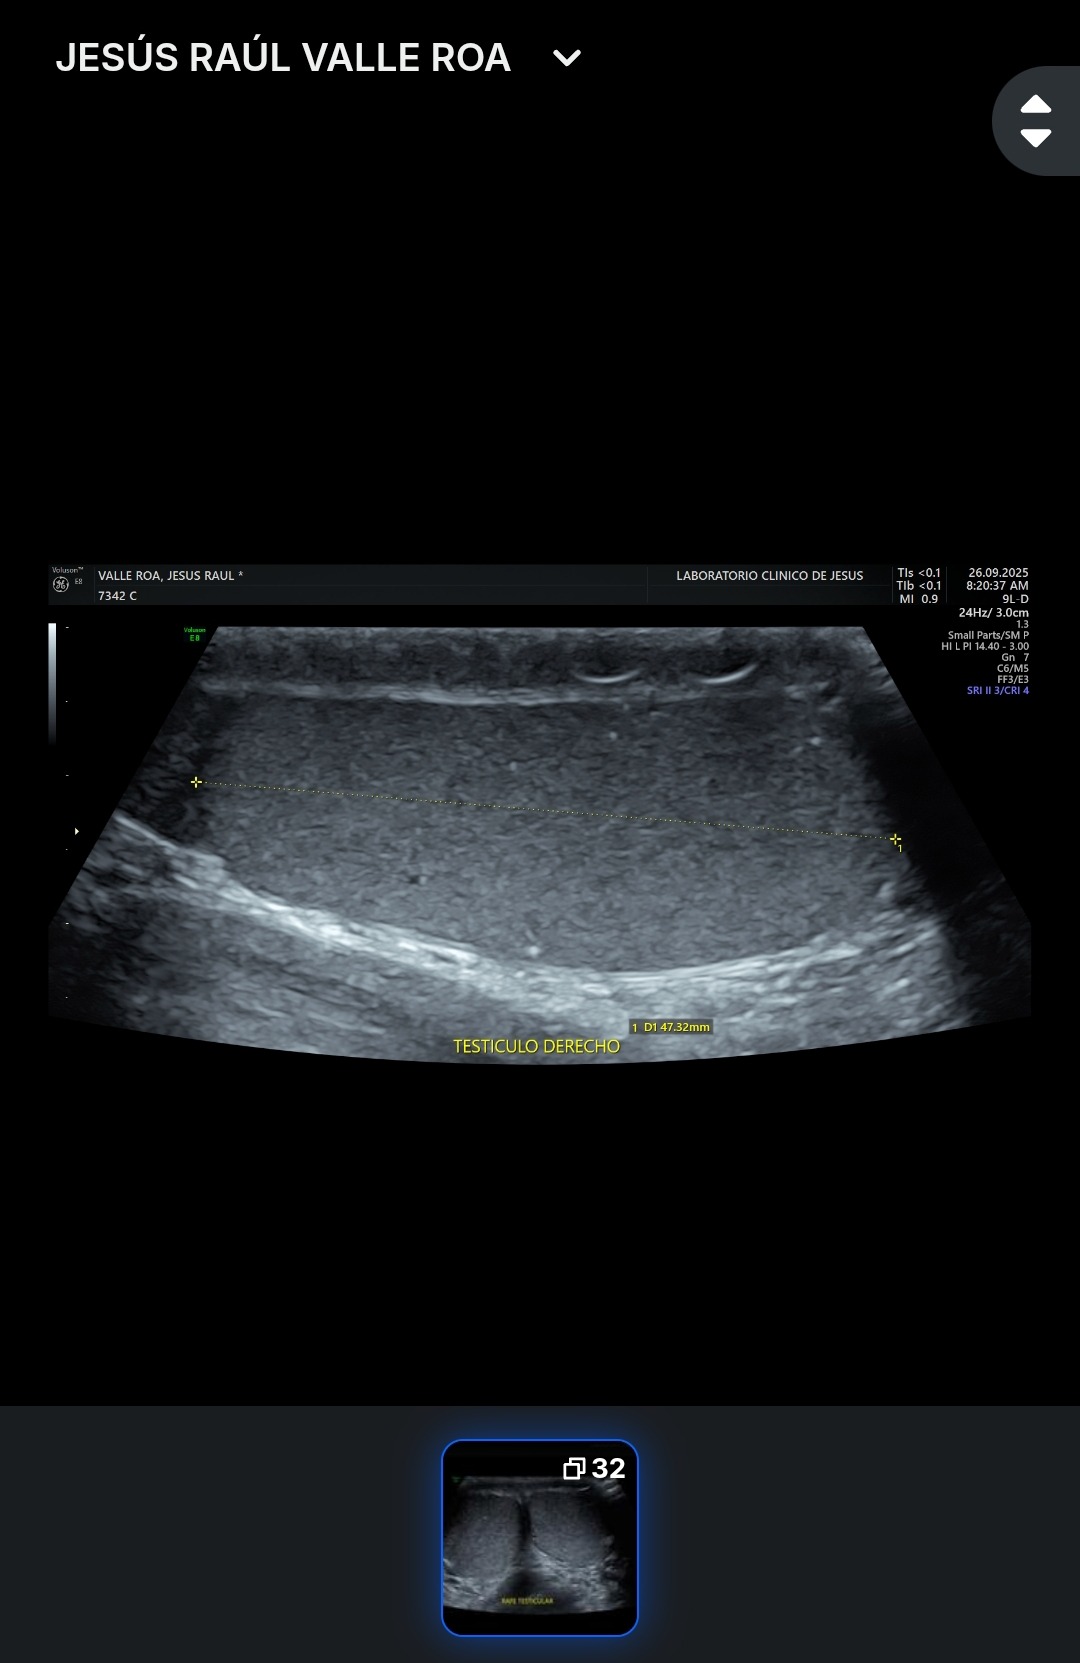

Hola me Llamo Raúl ,tengo 25 años , soy de la CDMX , me atrevo a pedir está ayuda , ya que desde hace unos meses empecé a sentir fuertes dolores en la zona de los testiculos, me hicieron estudios Doppler Testiculares, me detectaron Varicocele de Grado 4 en ambos testículos y microlitiasis testicular en ambos testículos y también tengo hernias en ambos conductos de los testiculos, sufro de fuertes dolores en ambos testículos , eso también está provocando que mi próstata este inflamada, no puedo mantenerme mucho tiempo parado o sentado, me duele mucho al orinar aveces con sangrado, llega el punto en que no puedo ya controlar la orina sale por su cuenta propia, no me atiendo en el IMSS porque el tiempo de espera es mucho , fui a médico particular y me dijeron que ya era urgente la operación porque la sangre no está llegando a los testiculos y se están muriendo, en estos momentos corro riesgo de Esterilidad , y las hernias si no se tratan pueden abrir mas y provocar que los intentos bajen por los conductos de los testiculos y sea una urgencia muy grava y riesgo de una extirpación del intestino si eso llega a pasar , pido su ayuda para poder llegar a esta cantidad, ya que en mi situación es muy difícil poder conseguir todo el dinero.